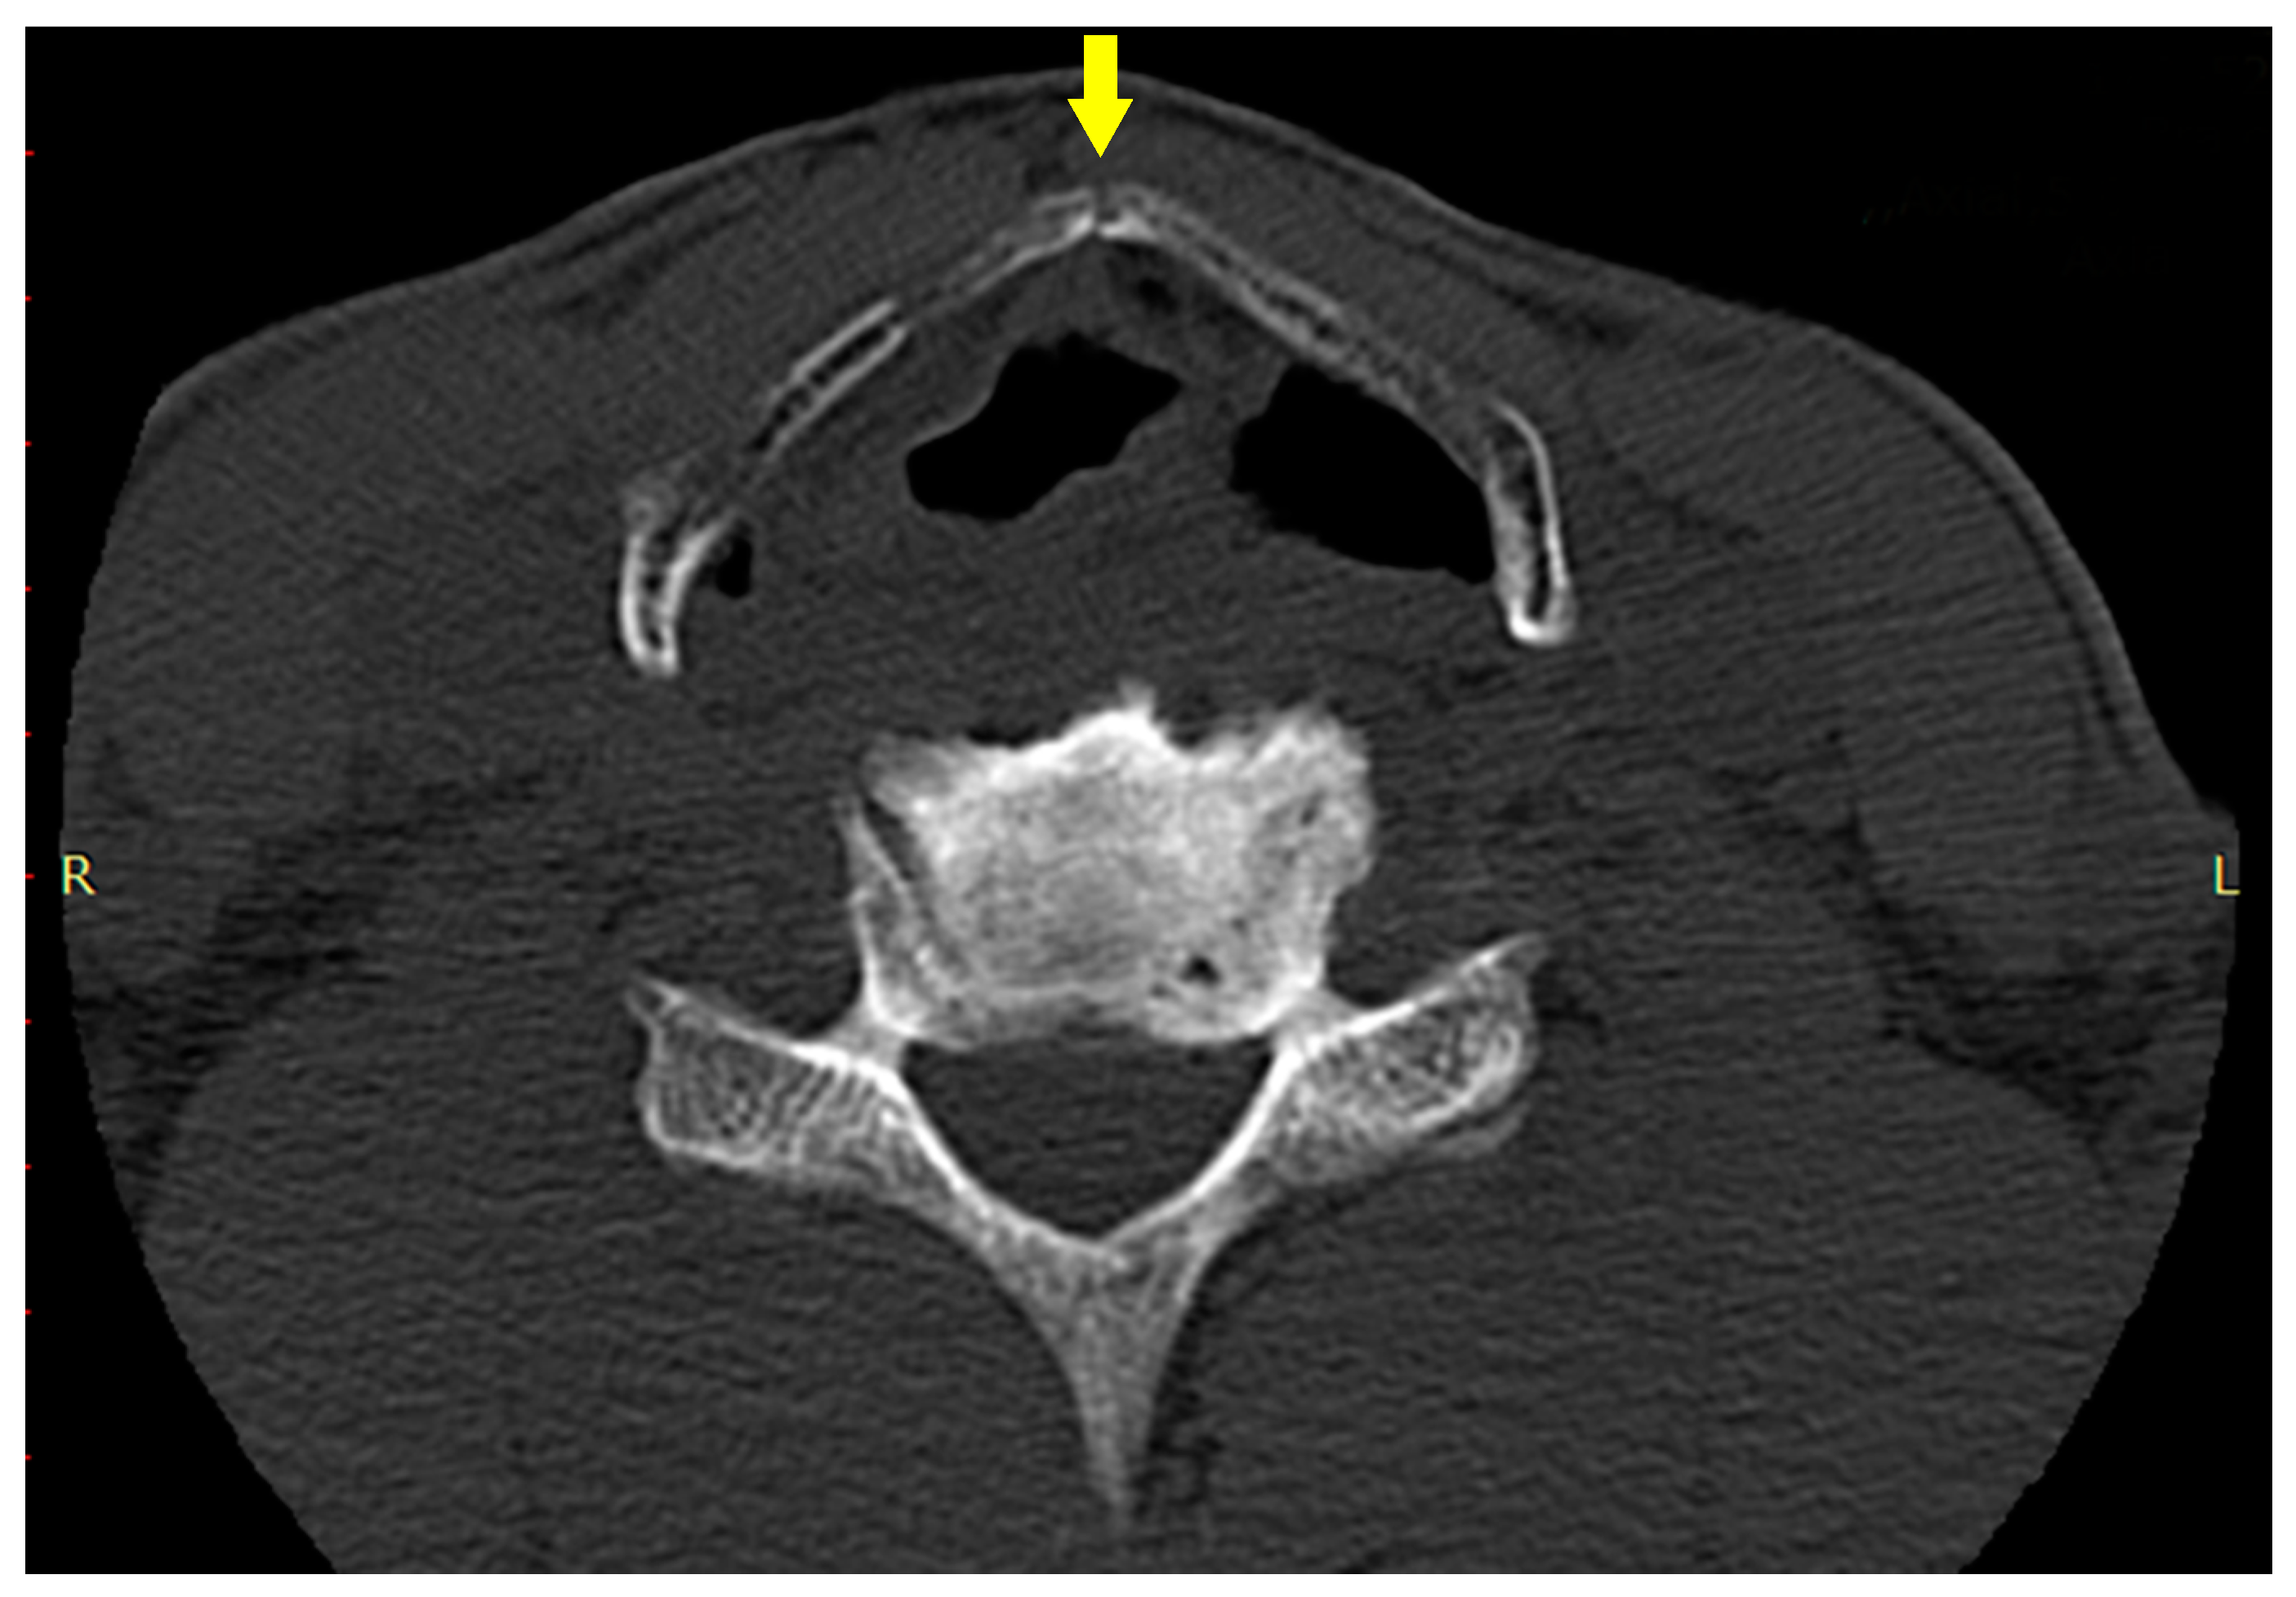

A Case of Fatal Asphyxia by a Barbell during a Bench Press

2. Case